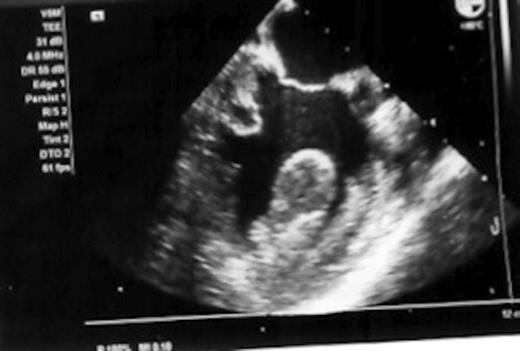

A postoperative transoesophageal echocardiogram (figure 3) was performed. This revealed impaired left ventricular function with a left ventricular clot. Specialist opinion on the echocardiography images was that the scans illustrated an extensive neoplasm in the left ventricle infiltrating both the myocardium and right ventricle leading to a diagnosis of sarcoma.